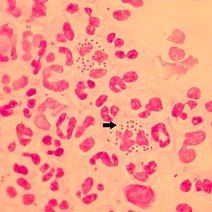

简介:脊髓灰质炎病毒,脊髓灰质炎病毒(poliovirus)是引起脊髓灰质炎的病毒。该疾病传播广泛,是一种急性传染病。病毒常侵犯中枢神经系统,损害脊髓前角运动神经细胞,导致肢体松弛性麻痹,多见于儿童,故又名小儿麻痹症。

脊髓灰质炎是病毒导致的。脊髓灰质炎是由于脊髓灰质炎病毒,侵害了脊髓前角灰质运动神经元,引起肌肉失支配遗留躯干以及四肢畸形,主要是由于病毒导致了神经源性的...2887人收听